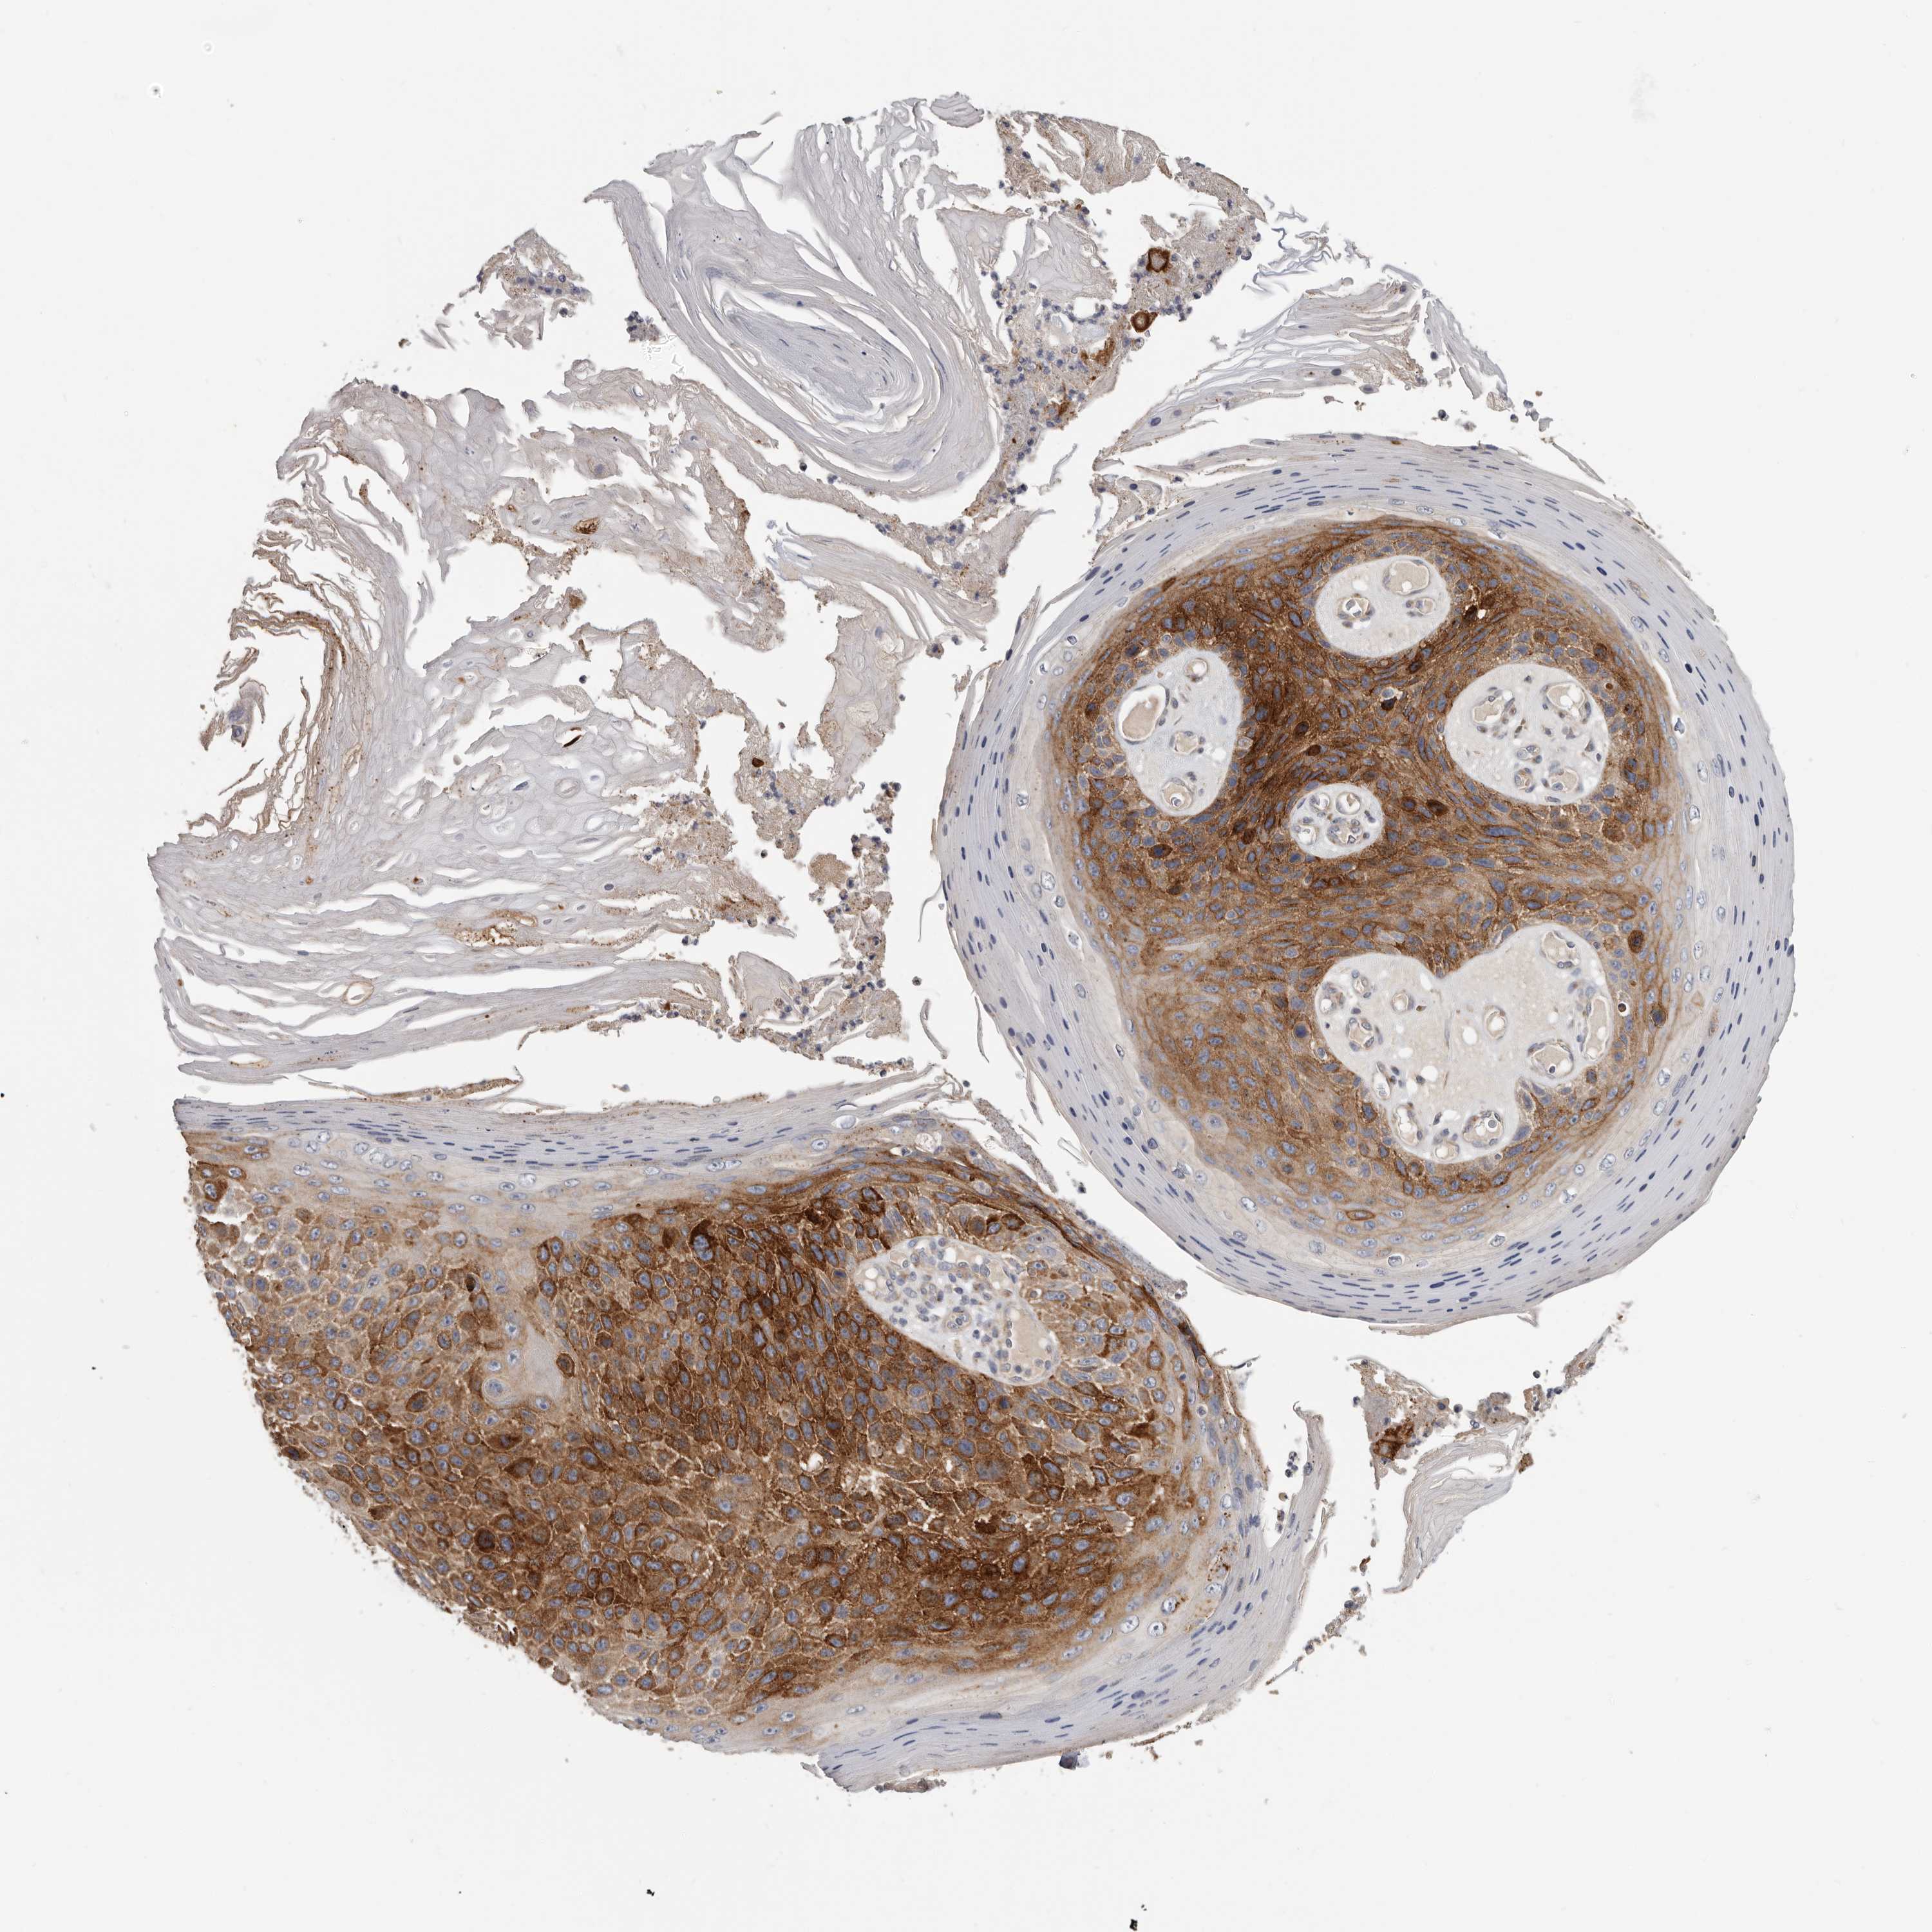

SKIN CANCER - Protein expressioni

A mouse-over function shows sample information and annotation data. Click on an image to view it in a full screen mode. Samples can be filtered based on level of antibody staining by selecting one or several of the following categories: high, medium, low and not detected. The assay and annotation is described here.

Each image is clickable and will lead to virtual microscopy that enables deeper exploration of all samples and also displays staining intensity scores, fraction scores and subcellular localization as well as patient and tissue information for each sample.

Antibody HPA028598

Squamous cell carcinoma, metastatic, NOS

Squamous cell carcinoma, NOS